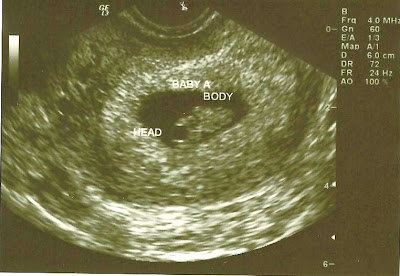

We had our 1st ultrasound at the "regular" OB yesterday. It was definitely different not being known by name by every nurse. ha. The Dr. was very nice though and the tech took a lot of time with my ultrasound. She tried really hard to guess the sex, but it is just too early to tell. boo! They looked amazing!!!

Baby A's heart rate was 154

Baby B's heart rate was 168

They measured the exact same- 12 weeks and 1 day (which is what I am )